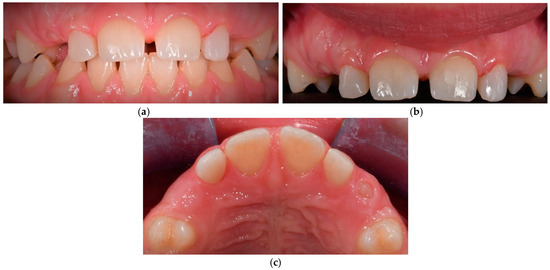

2.1. Case 1

2.1.1. Patient Presentation

2.1.2. Clinical Findings

2.1.3. Diagnosis and Assessment

2.1.4. Intervention Types Considered

2.1.5. Therapeutic Intervention